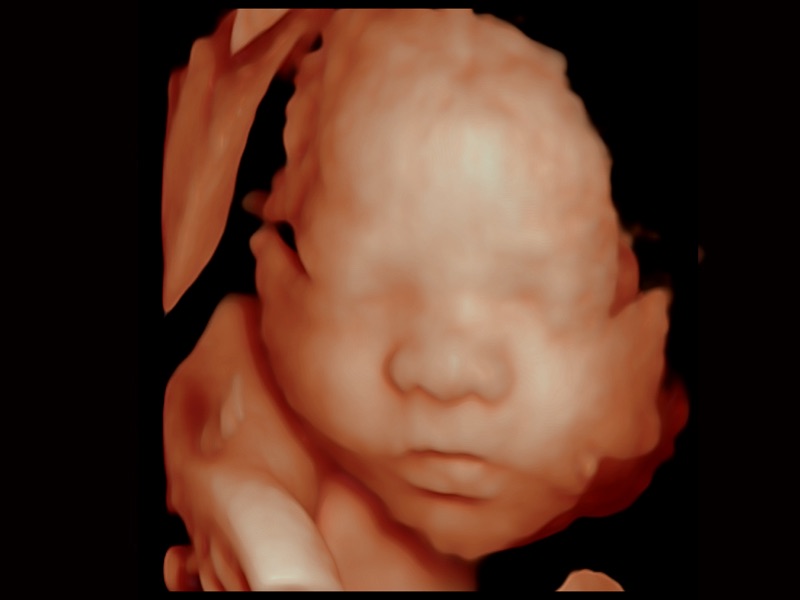

• 妇产科应用

• 光影成像

临床图